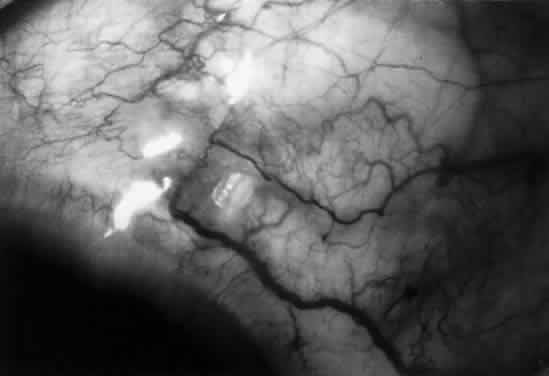

The filtration site is placed posteriorly near the equator in the latest generation of shunts. The morphologic features of these blebs are different from those of functional blebs at the limbus, as seen with a trabeculectomy. They are typically thick-walled, with prominent conjunctival vascularity, and are elevated over the reservoir (Fig. 1). Although the silicone tube and PMMA plates of the Molteno shunt are biologically inert and do not produce tissue necrosis, a thick fibrous capsule envelops the reservoir and tube (Fig. 2)25–29

Fig. 2. Histologic features of bleb surrounding a Molteno reservoir.

These histopathologic findings are similar to those reported for the Schocket tube,28 Baerveldt tube,29 and White pump shunt.24 The shunt apparatus is not degraded; it remains intact, with little or no adjacent inflammatory response and without fibrous adhesion to the implant. In contrast, a case report of an original Krupin valve composed of Supramid* describes significant biodegradation, with loss of tensile strength, attenuation, and fracture.30

The fibrous capsule that may originate from the episclera24 is relatively acellular and composed of scattered fibroblasts, collagen, and glycosaminoglycans.25,28 Aqueous is thought to pass through the fibrous capsule and into the orbital circulation through capillaries and lymphatics in addition to conjunctival circulation.25,28 Schocket used horseradish-peroxidase as a tracer and showed that aqueous could pass through the orbital vessels.28 In that study, the reservoirs preserved an area for bleb formation that had a relatively large surface area from which aqueous diffused. Orbital outflow, mechanical maintenance of a bleb zone, and a large surface area distinguish posterior tube shunts from limbal filtering operations and help to explain their success in the treatment of difficult cases of glaucoma.